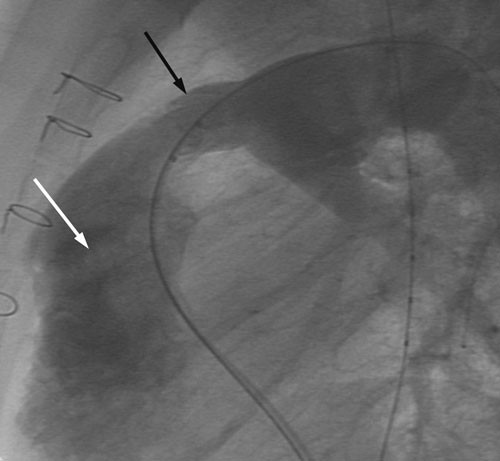

Kateteriseringsprosedyren blir gjennomført i samsvar med anbefalingene fra ledende internasjonale sentre og fra produsenten av perkutane kateterbaserte klaffer (7, 8). Pasientene er rutinemessig i generell anestesi under hele prosedyren, og det gis heparin intravenøst 100 IE/kg ved oppstart, etterfulgt av mindre påfyllingsdoser dersom prosedyren varer mer enn én time. Det gis antibiotika (Keflin 30 mg/kg) som en engangsdose. Det blir først foretatt en alminnelig høyresidig hjertekateterisering med tilgang fra lyskevene eller halsvene, trykkmålinger i høyre atrium, høyre ventrikkel og lungearterien, og angiografi med kontrastinjeksjon i høyre ventrikkel. Dette gir informasjon om stenose- og insuffisiensgrad i høyre ventrikkel-utløp, og også en detaljert anatomisk fremstilling av det området der den kunstige pulmonalklaffen skal forankres; sistnevnte har stor betydning for at prosedyren skal bli vellykket (fig 1). Med tilgang fra femoralarterie utføres dessuten koronarangiografi for å forsikre at koronararteriene ikke avklemmes når stenten plasseres i pulmonalutløpet.

Den kunstige pulmonalklaffen er fremstilt av halsvene fra kalv; klaffene i disse venene har en trikuspid anatomi som har stor likhet med humane pulmonalklaffer (8). Etter preparering i glutaraldehyd er venestump med klaff montert inn i en metallstent og forankret i denne med tallrike mikroskopiske suturer. Dette produktet (Melody, Medtronic, California, USA) kan komprimeres og føres inn i høyre ventrikkel-utløp gjennom et spesialdesignet kateter. Når rett posisjon oppnås, blir stenten med påsydd klaff ekspandert ved hjelp av ballonger slik at ytterveggene i stenten presses kraftig mot innsiden av høyre ventrikkels utløp. Dermed utvides utløpet, samtidig som stenten med klaff blir forankret. Trykkmålinger og angiografi etter innsetting blir brukt for å evaluere resultatet av prosedyren (fig 2). Alle stegene i denne prosedyren er utført i henhold til retningslinjer utarbeidet gjennom en serie europeiske møter gjennomført i regi av produsenten, og med deltakere fra alle de store sentrene i Europa. Vårt fagmiljø har bidratt aktivt i denne møteserien.

Innsetting av kunstig pulmonalklaff medførte signifikant lavere systolisk trykk i høyre ventrikkel hos samtlige pasenter; medianverdien ble redusert fra 60 mm Hg til 38 mm Hg (tab 3). Samtidig steg det diastoliske trykket i pulmonalarterien etter prosedyren hos et flertall av pasientene (tab 3, medianverdien er likevel den samme pga. liten spredning i materialet), og kontrastinjeksjon viste ingen eller minimal pulmonalinsuffisiens (fig 1 og 2). Median liggetid i avdelingen var to dager (maksimal liggetid fire dager for én person); pasientene ble deretter skrevet ut til hjemmet.